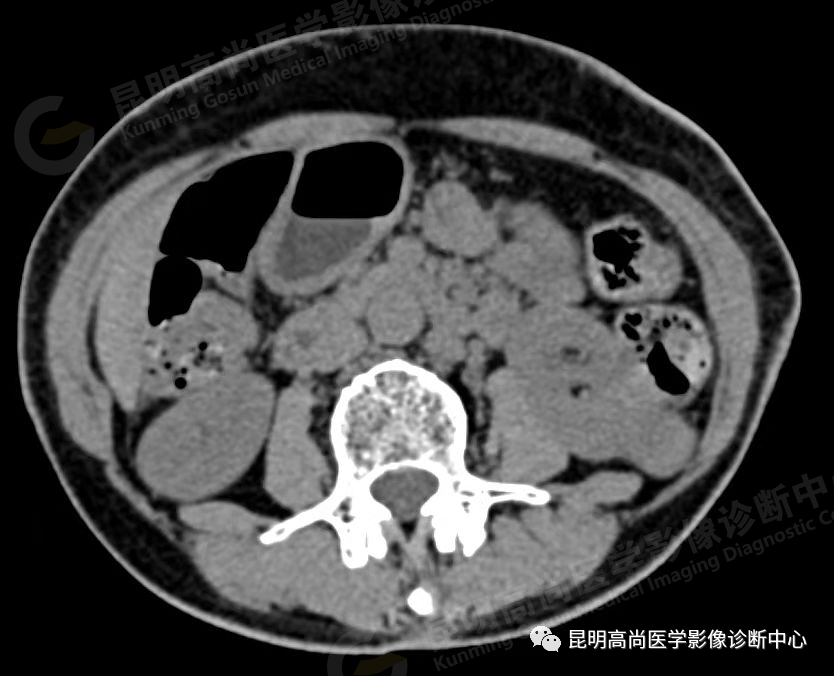

于 2021 年 9 月 17 日至本中心行 CT 平扫+增强检查;

左肾下份占位病变,多考虑恶性肿瘤。请结合临床及相关检查。

(2)CT 检查

能清晰地显示直径 1 cm 以上肾实质内肿块,肿瘤边缘不规整,呈圆形或分叶状;

平扫时,肿瘤的密度随肿瘤的细胞成分不同而略有差异,透明细胞癌的密度低于正常肾实质,而颗粒细胞癌的密度略高于正常;

增强扫描后,肿瘤密度可不同程度地增强,但仍低于正常肾组织,由于增加了肿瘤与肾组织间的密度差,可以更清楚地显示肿瘤大小与分界线;

肿瘤内常有出血、液化和坏死区,使瘤体密度变为不均性;5%-10% 肿瘤内可见密度增强的钙化灶,位于瘤体中央或边缘处;

CT 对肾细胞癌能精确估计病变的大小和范围,还可了解周围有无浸润、淋巴及远处有无转移,从而对肾癌的分期提供重要的依据。